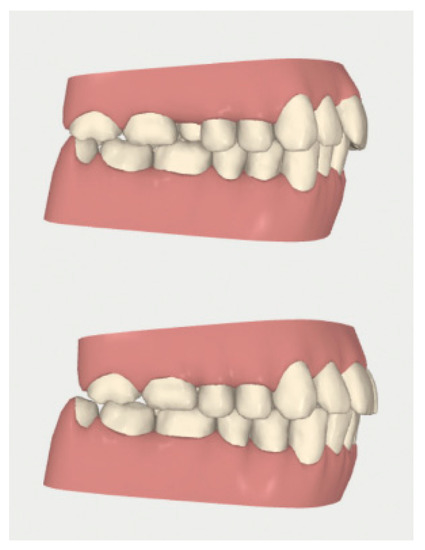

2.3.1. Example—Anterior Open-bite

2.3.2. Example 2—Extraction Space Closure